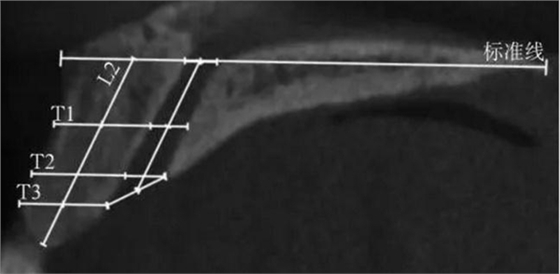

(1)正中矢狀面(圖1~3)。所使用的測(cè)量參數(shù)及其定義如下所述。鼻腭管高位直徑(S1):標(biāo)準(zhǔn)線交鼻腭管處的管徑;鼻腭管中位直徑(S2):鼻腭管長(zhǎng)軸中點(diǎn)處的管徑;鼻腭管低位直徑(S3):管后壁腭側(cè)骨最低點(diǎn)至對(duì)應(yīng)管前壁的水平管徑;切牙孔開(kāi)口直徑(S4):管后壁腭側(cè)骨最低點(diǎn)至唇側(cè)骨低位厚度和管前壁交點(diǎn)的直線距離。唇側(cè)骨高位厚度(T1):S2平面處唇側(cè)骨板水平厚度;唇側(cè)骨中位厚度(T2):S3平面處唇側(cè)骨板水平厚度;唇側(cè)骨低位厚度(T3):唇側(cè)骨最凸處骨板水平厚度。鼻腭管長(zhǎng)度(L1):S1與S4中點(diǎn)間的距離;唇側(cè)骨長(zhǎng)度(L2):唇側(cè)骨下端最低點(diǎn)經(jīng)T1、T3中點(diǎn)至標(biāo)準(zhǔn)線的直線長(zhǎng)度。鼻腭管傾斜角度(A1):L1和標(biāo)準(zhǔn)線的垂線所成角度;唇側(cè)骨傾斜角度(A2):L2和標(biāo)準(zhǔn)線的垂線所成角度。

T1:唇側(cè)骨高位厚度;

T2:唇側(cè)骨中位厚度;

T3:唇側(cè)骨低位厚度;L2:唇側(cè)骨長(zhǎng)度。

圖 2 矢狀面唇側(cè)骨板測(cè)量方法

Fig 2 Measurements ofcorresponding buccal bone